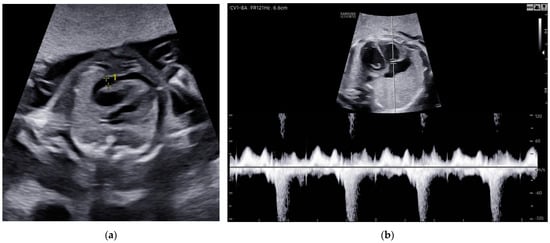

Also, a total resolution of fetal hydrops was observed (Figure 6).

Figure 6. Case 6: Total resolution of ascites (a) before first intrauterine transfusion, 24 weeks of gestational age; (b) 2 weeks after second intrauterine transfusion, 28 weeks of gestation.